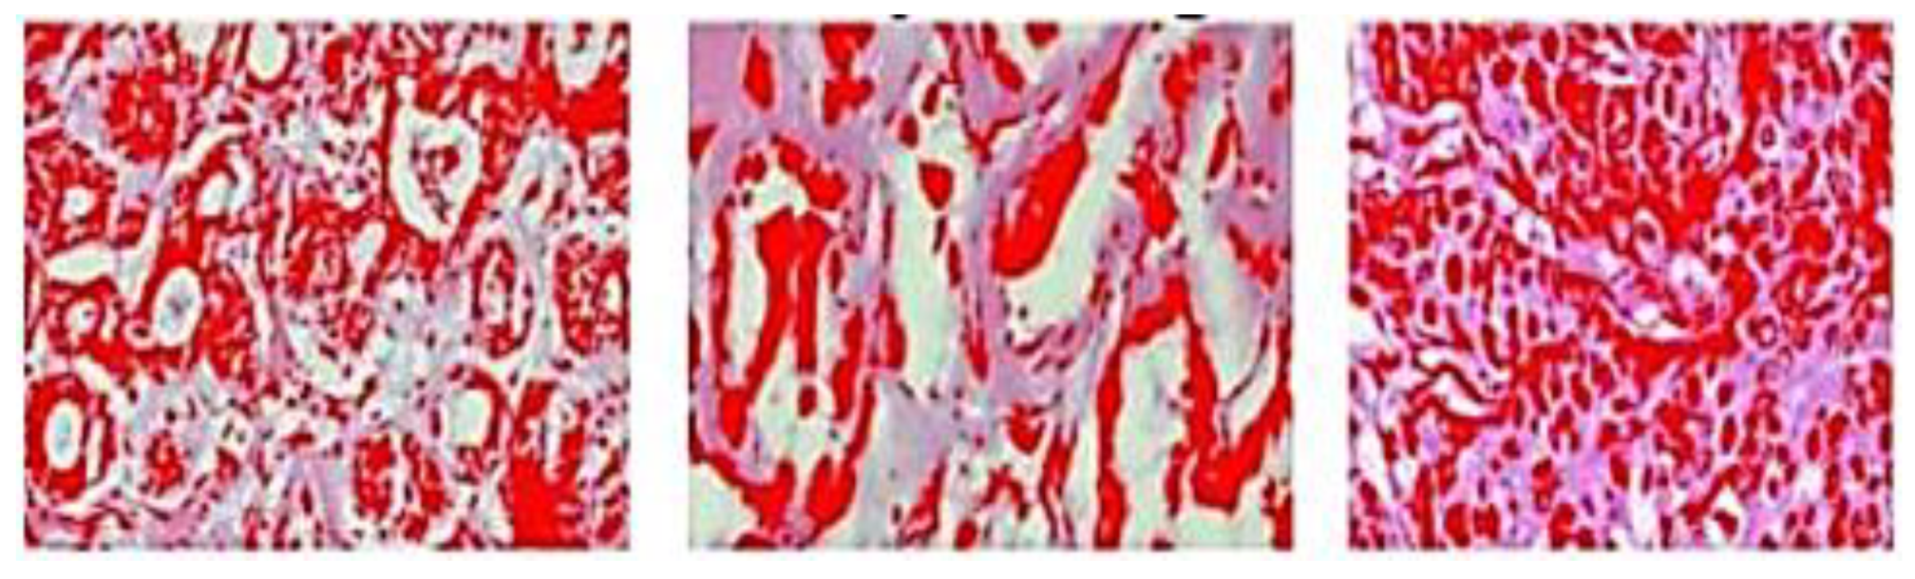

| 2021 | S. Alanazi et al. [90] | Kaggle 162 H&E - Invasive Ductal Carcinoma (IDC) Segmentation | Convolutional Neural Network (CNN) | Image | IDC positive and IDC negative | CNN = 87 |